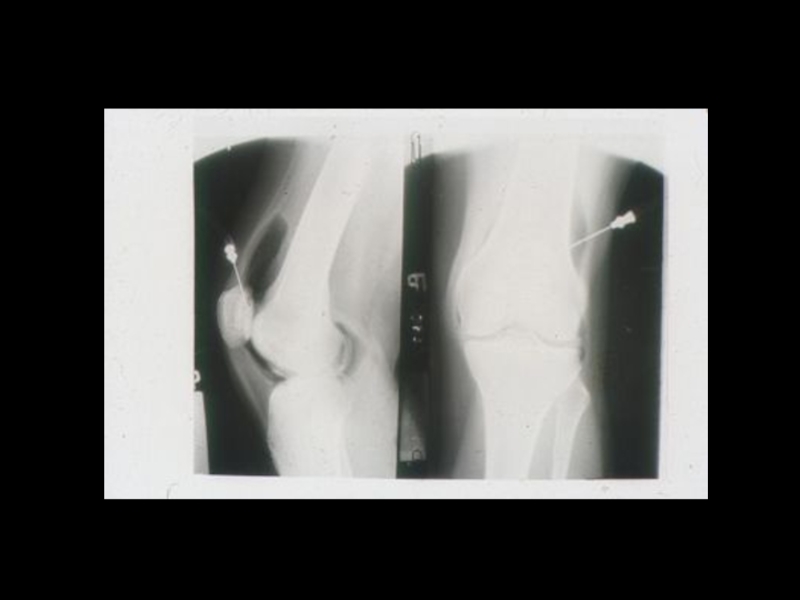

3. Специальные методы

(урография, бронхография, ангиография,

лимфография, пневмоартрография и другие)

Слайд 37Задачи искусственного контрастирования органов:

1. Получение изображения органов , не обладающих

естественной контрастностью

2. Повышение разрешающей способности методов, за

счет повышения качества изображения и создания

эффекта «усиления»

3. Осуществление контроля при проведении

интервенционных мероприятий, проводимых с

помощью лучевых методик.